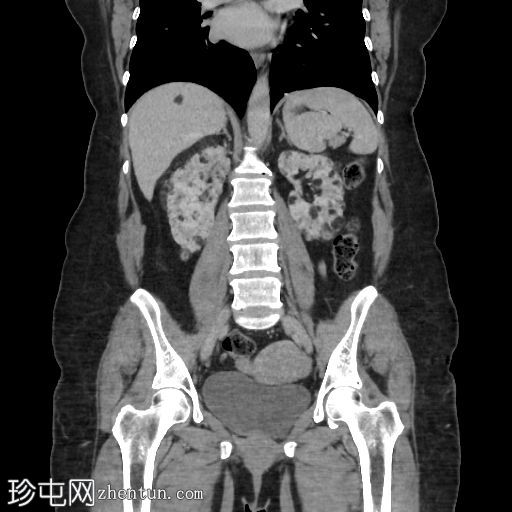

冠状位增强扫描

门静脉期

肝脏内可见多发边界清晰的脂肪结节状病变,最大病变位于肝脏VII段,直径15 mm

双肾可见多发脂肪肿块,右肾最大病变直径达45 mm,左肾最大病变直径20 mm

椎体可见小的硬化性骨病变

肾血管平滑肌脂肪瘤是结节性硬化症最常见的腹部表现,通常为多发性、双侧性,且体积大于散发性病变。血管平滑肌脂肪瘤。肝脏血管平滑肌脂肪瘤虽然不常见,但却是公认的肾外表现,其影像学特征与肾脏血管平滑肌脂肪瘤相似,包括CT扫描可见肉眼可见的脂肪,这使得诊断成为可能,且无需侵入性检查。

识别包括多发性含脂肪肾血管和肝血管平滑肌脂肪瘤以及多灶性骨硬化病变在内的影像学表现至关重要,因为这有助于确诊结节性硬化症,并避免不必要的活检或其他侵入性检查。